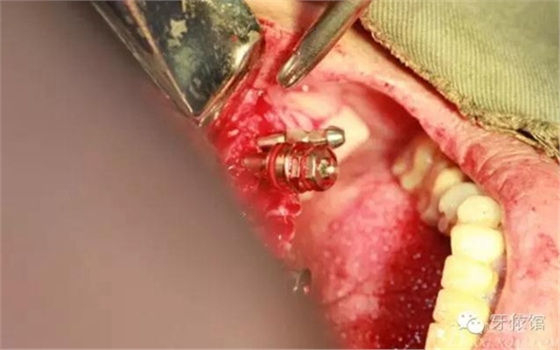

切牙壓孔內(nèi)植入植體,扭力50n

左右3牙位分別植入一顆